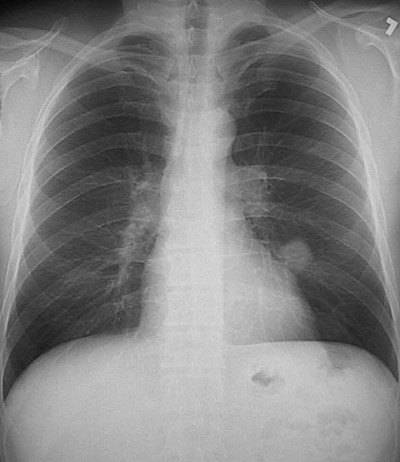

Click on the hamartoma in the chest radiograph above:

The PA chest radiograph seen here demonstrates a discrete "coin lesion" that did not greatly increase in size over time. A wedge resection was performed, and the mass proved to be a pulmonary hamartoma.